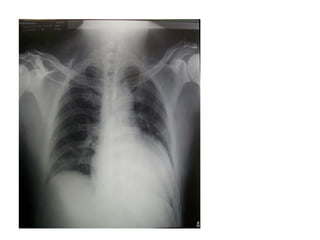

• 3-RX de Tórax- mostrara una

cardiomegalia franca junto con el índice

cardiotorácico. ( normal < 0.5 cm)